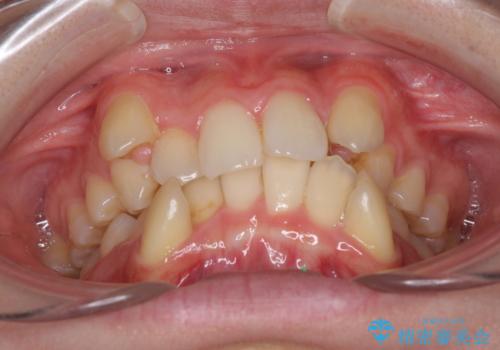

- 上下の八重歯や乱杭歯を気にして来院され患者様です。

スペースを確保するため、上下左右の第一小臼歯を抜歯し、ワイヤー装置に矯正することとしました。